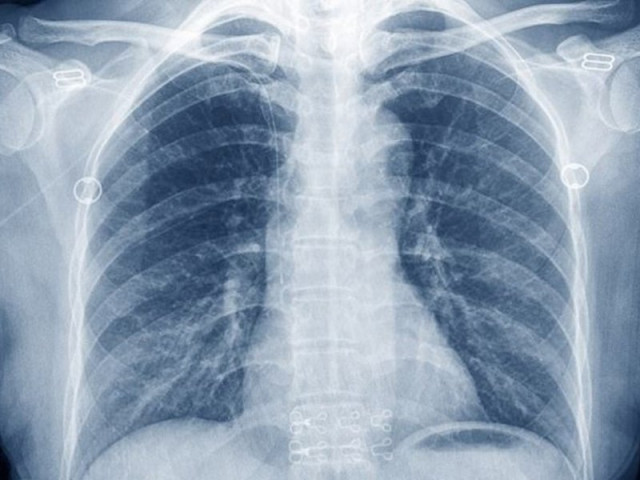

Онкологи назвали кашель с кровью основным симптомом рака легких

Врач Ростова в качестве основных симптомов назвал кровавый кашель, одышку, боль в груди, охриплость, потерю веса и общее недомогание (повышение температуры,

Врач Ростова в качестве основных симптомов назвал кровавый кашель, одышку, боль в груди, охриплость, потерю веса и общее недомогание (повышение температуры, слабость и утомляемость)

Если вы заметили у себя хотя бы один из этих симптомов, обратитесь к врачу и попросите направление на компьютерную томографию грудной клетки. — Чем раньше выявлен рак легкого, тем выше вероятность его излечения. Если отложить диагностику и не начать лечение на ранней стадии, злокачественный процесс может распространиться за пределы органа.

Олег Кит, директор Национального центра медицинской онкологии Минздрава России, доктор медицинских наук, профессор, академик РАН, говорит На ранних стадиях рака легкого заболевание может протекать бессимптомно. Чтобы выявить это, необходимо регулярно проходить обследование, например, во время медосмотров.

Дмитрий Харагезов, кандидат медицинских наук, заведующий отделением торакальной онкологии НМИЦ Минздрава России, утверждает, что 90% пациентов с этим видом рака — курильщики. В том числе и пассивные курильщики.

— Отказ от курения — основной способ профилактики рака легких. В группу риска также входят люди, работающие на вредных производствах. Поэтому при работе с цементом или асбестовой пылью необходимо использовать средства индивидуальной защиты».